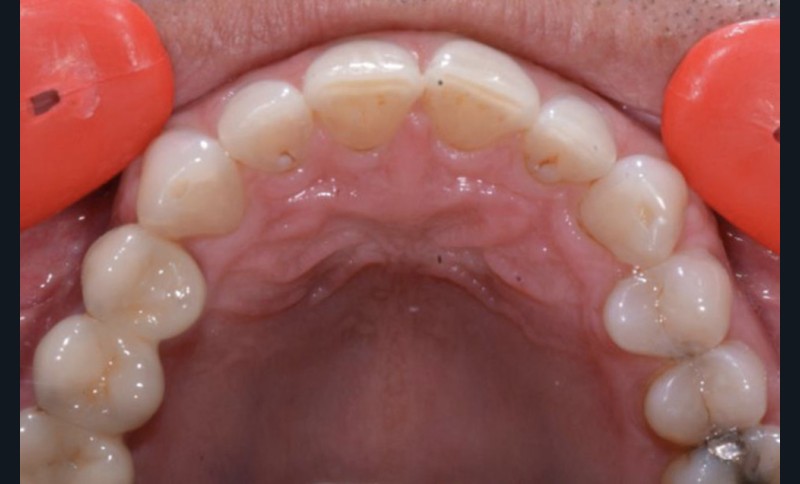

Présentation du cas clinique (fig. 1 à 3)

Le patient, âgé de 58 ans, présente un encombrement dentaire mandibulaire de 5 mm dans un contexte squelettique hypodivergent.

À la radiographie panoramique, on constate une lésion apicale sur 15 et une atteinte inter radiculaire sur 16 ainsi qu’une légère rotation de 21 sans gêne pour le patient.